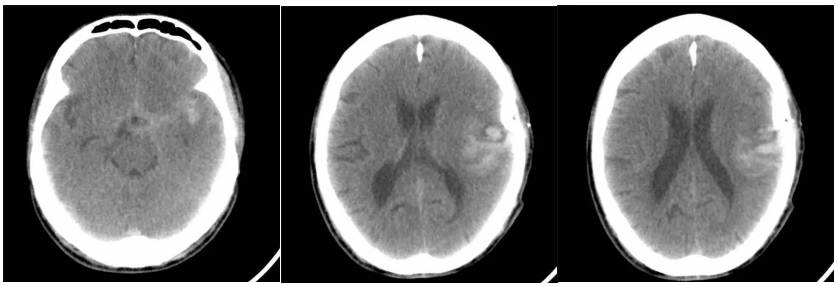

急诊室脑梗塞移动CT床旁脑部扫描

脑科ICU脑出血移动CT床旁脑部扫描